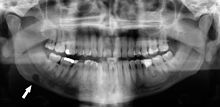

Dental panoramic radiograph showing Stafne defect in the right mandible, below the inferior alveolar nerve canal (arrowed, appears on lower left of image). This x-ray was taken for an unrelated assessment of wisdom teeth, and the Stafne defect was a chance finding.

Stafne's defect is usually discovered by chance during routine dental radiography.[4] Radiographically, it is a well-circumscribed, monolocular, round, radiolucent defect, 1–3 cm in size, usually between the inferior alveolar nerve (IAN) and the inferior border of the posterior mandible between the molars and the angle of the jaw. It is one of the few radiolucent lesions that can occur below the IAN. The border is well corticated and it will have no effect on the surrounding structures. Computed tomography (CT) will show a shallow defect through the medial cortex of the mandible with a corticated rim and no soft tissue abnormalities, with the exception of a portion of the submandibular gland. Neoplasms, such as metastatic squamous cell carcinoma to the submandibular lymph nodes or a salivary gland tumour, could create a similar appearance but rarely have such well defined borders and can usually be palpated in the floor of the mouth or submandibular triangle of the neck as a hard mass. CT and clinical exam is typically sufficient to distinguish between this and a Stafne defect. The Stafne defect also tends to not increase in size or change in radiographic appearance over time (hence the term "static bone cyst"), and this can be used to help confirm the diagnosis.[4] Tissue biopsy is not usually indicated, but if carried out, the histopathologic appearance is usually normal salivary gland tissue. Sometimes attempted biopsy of Stafne defects reveals an empty cavity (possibly because the gland was displaced at the time of biopsy), or other contents such as blood vessels, fat, lymphoid or connective tissues. Defects of the anterior lingual mandible may require biopsy for correct diagnosis at this unusual location.[2] The radiolucent defect here may be superimposed on the lower anterior teeth and be mistaken for an odontogenic lesion. Sometimes the defect may interrupt the contour of the lower border of the mandible, and may be palpable. Sialography may be sometimes used to help demonstrate the salivary gland tissue within the bone.